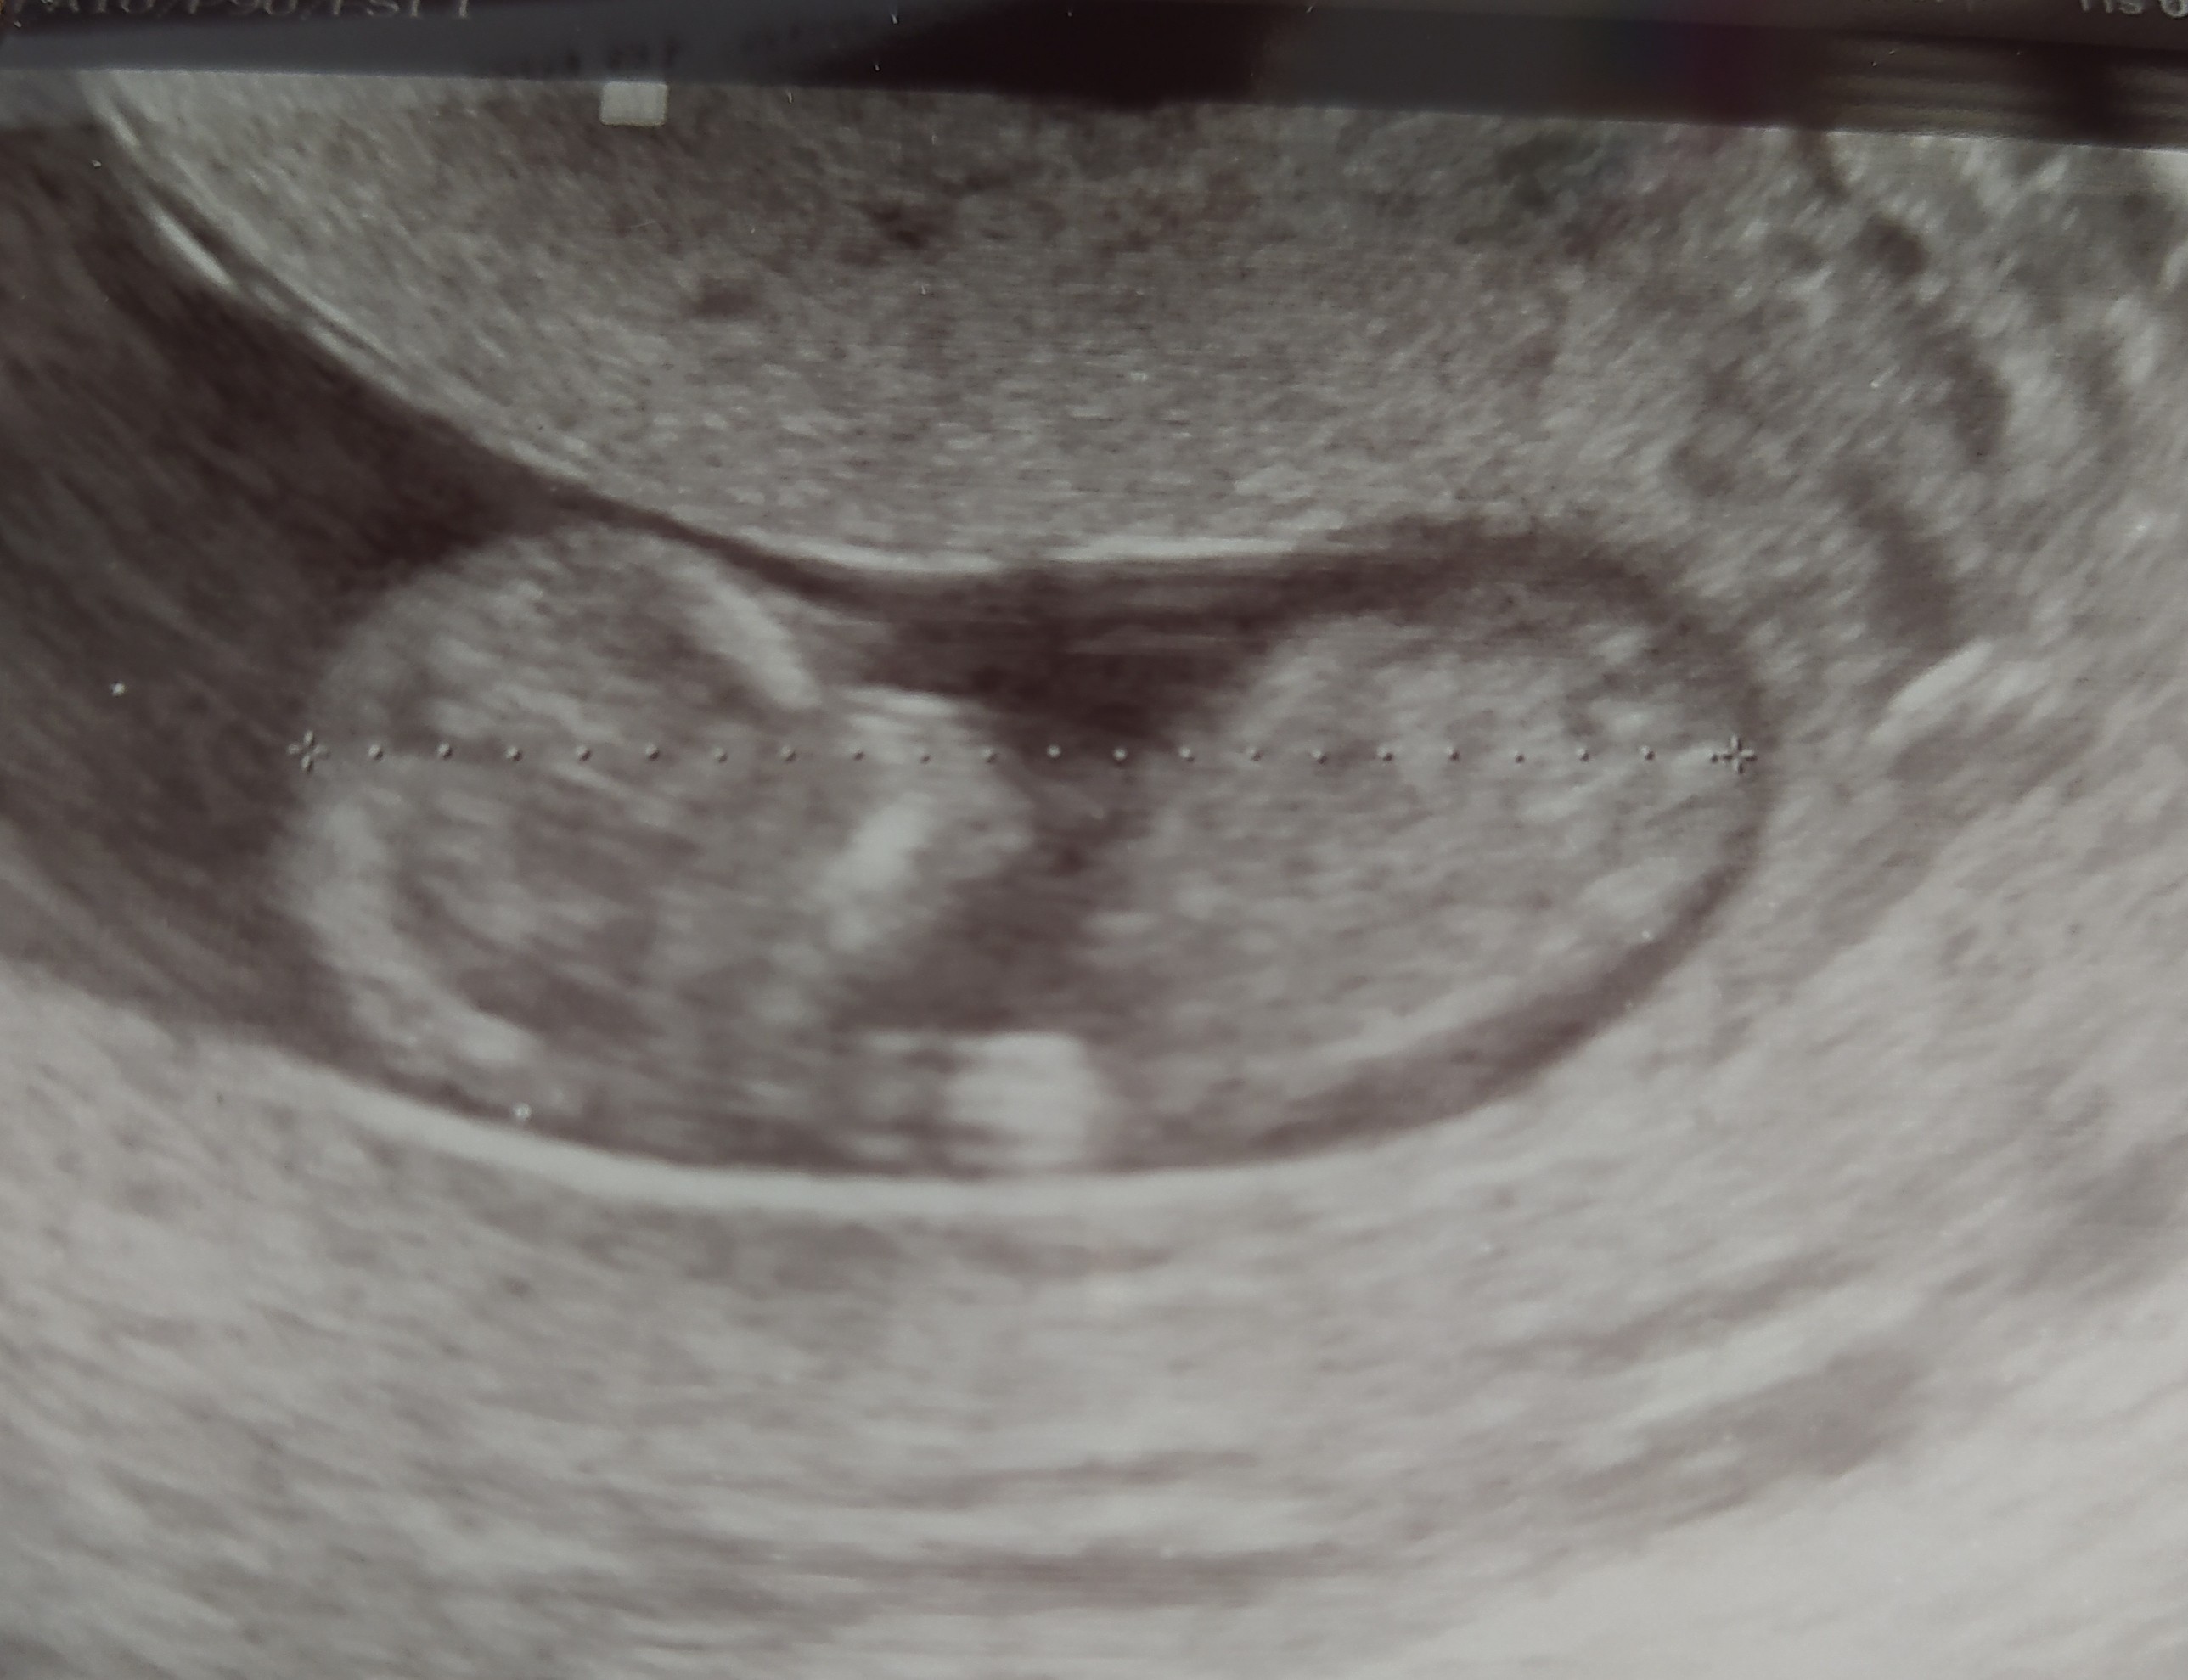

Hej dziewczyny 😊 dawno nic nie pisałam, czasu brak. Jestem po wizycie u gina, Mikrusek ma 4 cm, serduszko bije, wszystko ok 😊 dzisiaj zaczęłam 11t. Badania prenatalne mam 4.03, wiek 35+ 😉 więc też mam stresa. Jeszcze nie zdecydowałam czy będę robiła dodatkowo Nifty 🤔 zapomniałam zapytać gina co on o tym myśli z tego stresu na wizycie🤦🏻‍♀️

• IMG_20210219_110859.jpg

IMG_20210219_110859.jpg

508,2 KB · Wyświetleń: 119